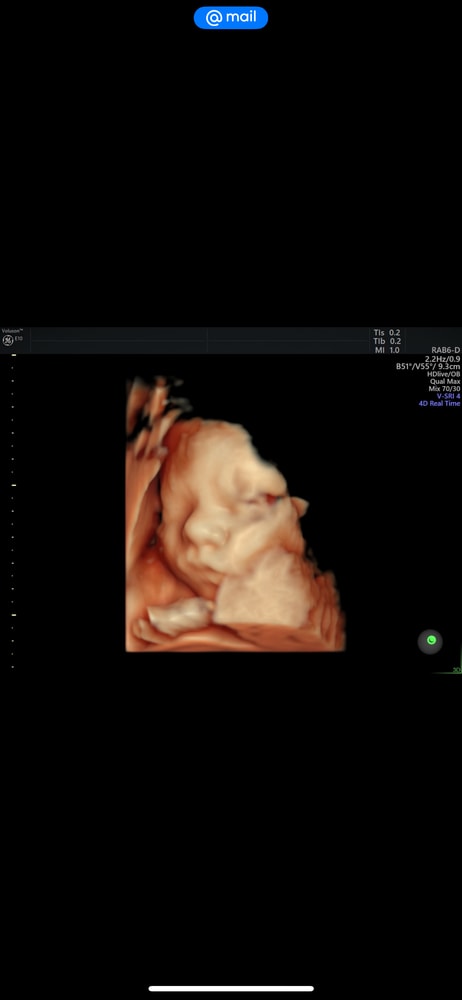

Деля , вот еще за 3 Нед до родов 😄 Изображение